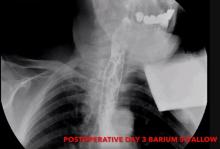

The operative time was 200 minutes. On postoperative day three, a barium swallow demonstrated that the esophagus was widely patent and had no leakage from either the diverticulectomy suture line or the myotomy. After a follow-up period of 14 months the patient is symptom free. In the authors’ opinion, this operation can be performed as a minimally invasive surgical procedure regardless of diverticula size. Technical factors also support this choice, including: better visualization of the esophagogastric junction, easier myotomy and performance of antireflux wrap, and better alignment of the stapler cartridge to the longitudinal axis of the esophagus. The only limiting factor is represented by the impossibility to extensively mobilize the lower esophagus.